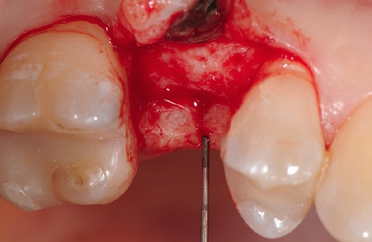

Unter Lokalanästhesie erfolgte nach krestaler Schnittführung die Aufklappung (Abb. 5) und die Aufbereitung des Implantatbettes gemäß dem chirurgischen Protokoll für NobelPearl mit den Bohrern des NobelPearl Surgical Tray. Nach Ankörnung mit dem Rosenbohrer wurde unter Beachtung der korrekten Implantatachse die 1. Bohrung mit dem zylindrischen Pilotbohrer Ø 2,3 mm auf die geplante Länge von 10 mm angelegt. Für die unterschiedlichen Längen stehen in der Folge formkongruente Profilbohrer zu Verfügung. So wird für die weitere Aufbereitung zunächst der Profilbohrer „small“, Länge 10 mm, Ø 3,3 mm (Farbcodierung violett), und danach der Profilbohrer „regular“, Länge 10 mm, Ø 4,2 mm (Farbcodierung gelb, hier mit Tiefenstopp), ausgewählt (Abb. 6).Da das NobelPearl-Implantat nicht selbstschneidend ist und beim Eindrehen des Implantats der Werkstoff Keramik keine Temperatur wie ein Titanimplantat ableitet, muss als letztes Instrument der Gewindeschneider auf die gesamte Implantatlänge eingesetzt werden.

Die Implantate wurden im Anschluss mit einer ausreichenden Primärstabilität von 30 Ncm und einem suprakrestalen Anteil 0,6 mm platziert. Diese suprakrestale Positionierung wird durch einen gegebenenfalls am Profilbohrer anbringbaren Tiefenstopp (Abb. 7) vereinfacht. Für das Einbringen der Implantate steht ein neues, zur „Inter-X“-Innenverbindung formschlüssiges Eindrehinstrument (Abb. 8) zu Verfügung, wodurch eine optimale Kraftübertragung während des Inserierens des Implantats gewährleistet wird (Abb. 9). Die Einheilkappen sind deutlich abgeflacht und ermöglichen einen einfachen primären Wundverschluss (Abb. 10 und 11). Im vorliegenden Fall verlief die Wundheilung komplikationslos. Nach einer auch für Keramikimplantate heute üblichen Einheilungszeit von 3 Monaten zeigten sich die Implantate in der Röntgenkontrollaufnahme stabil osseointegriert (Abb. 12). Es fanden sich an beiden Implantat-Loci entzündungsfreie Weichgewebsverhältnisse, woraufhin mit der prothetischen Versorgung des Implantats begonnen werden konnte.